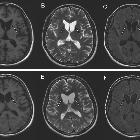

MRI

- T2/FLAIR:

- generally:

- atrophy and gliosis of the basal ganglia are typical, and so these deep brain structures may appear reduced in size

- regions of the basal ganglia may be hyperintense, indicating gliosis

- specifically:

- the head of the caudate is most often affected in ChAc, with the putamen, globus pallidus and substantia nigra affected to a lesser extent

- bilateral atrophy of the caudate and putamen is again observed in MLS and HDL2

- PKAN is characterized by an eye of the tiger iron deposition pattern - a round hyperintensity in the anteromedial globus pallidus